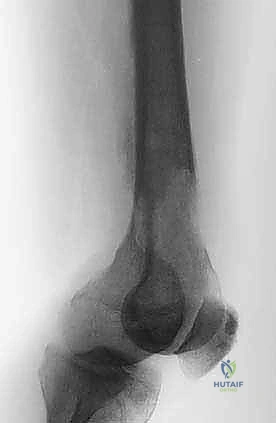

3. الجزء السفلي من عظم الفخذ (Distal Femur)

هذا الجزء يتسع ليشكل اللقمتين الفخذيتين (Condyles) اللتين تتمفصلان مع عظم الظنبوب (القصبة) لتكوين مفصل الركبة. النقائل في هذه المنطقة تؤثر بشكل مباشر على ميكانيكا الركبة وتسبب آلاماً شديدة عند ثني أو فرد الساق. الجراحة هنا تتطلب دقة متناهية للحفاظ على أربطة الركبة (الصليبية والجانبية) أو استبدال المفصل بالكامل بمفصل صناعي للأورام إذا كان التدمير العظمي واسعاً.

- الأشعة السينية العادية (X-rays): هي الخطوة الأولى دائماً. تظهر النقائل الحالة للعظم كبقع داكنة (ثقوب) في العظم، بينما تظهر النقائل البانية كبقع بيضاء كثيفة. الأشعة السينية ضرورية لتقييم خطر الكسر.

- التصوير المقطعي المحوسب (CT Scan): يقدم تفاصيل ثلاثية الأبعاد لا مثيل لها لجودة القشرة العظمية المتبقية. يساعد الجراح في التخطيط لحجم المسامير أو الصفائح المطلوبة، وتقييم مدى تدمير العظم.